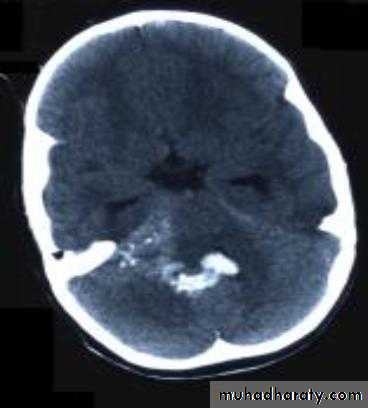

• Computed Tomography scan (CT scan) with/without contrast• Magnetic Resonance Imaging (MRI) with/without contrast